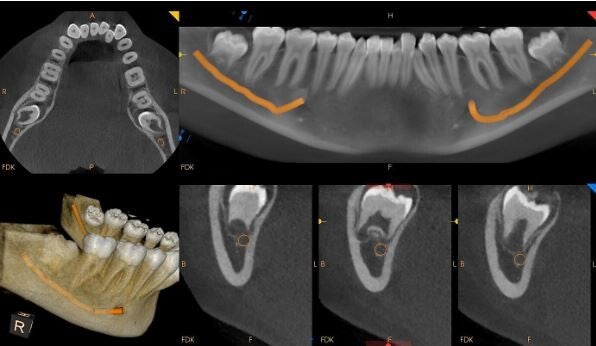

Medium F.O.V CBCT

Maxilla or Mandible.